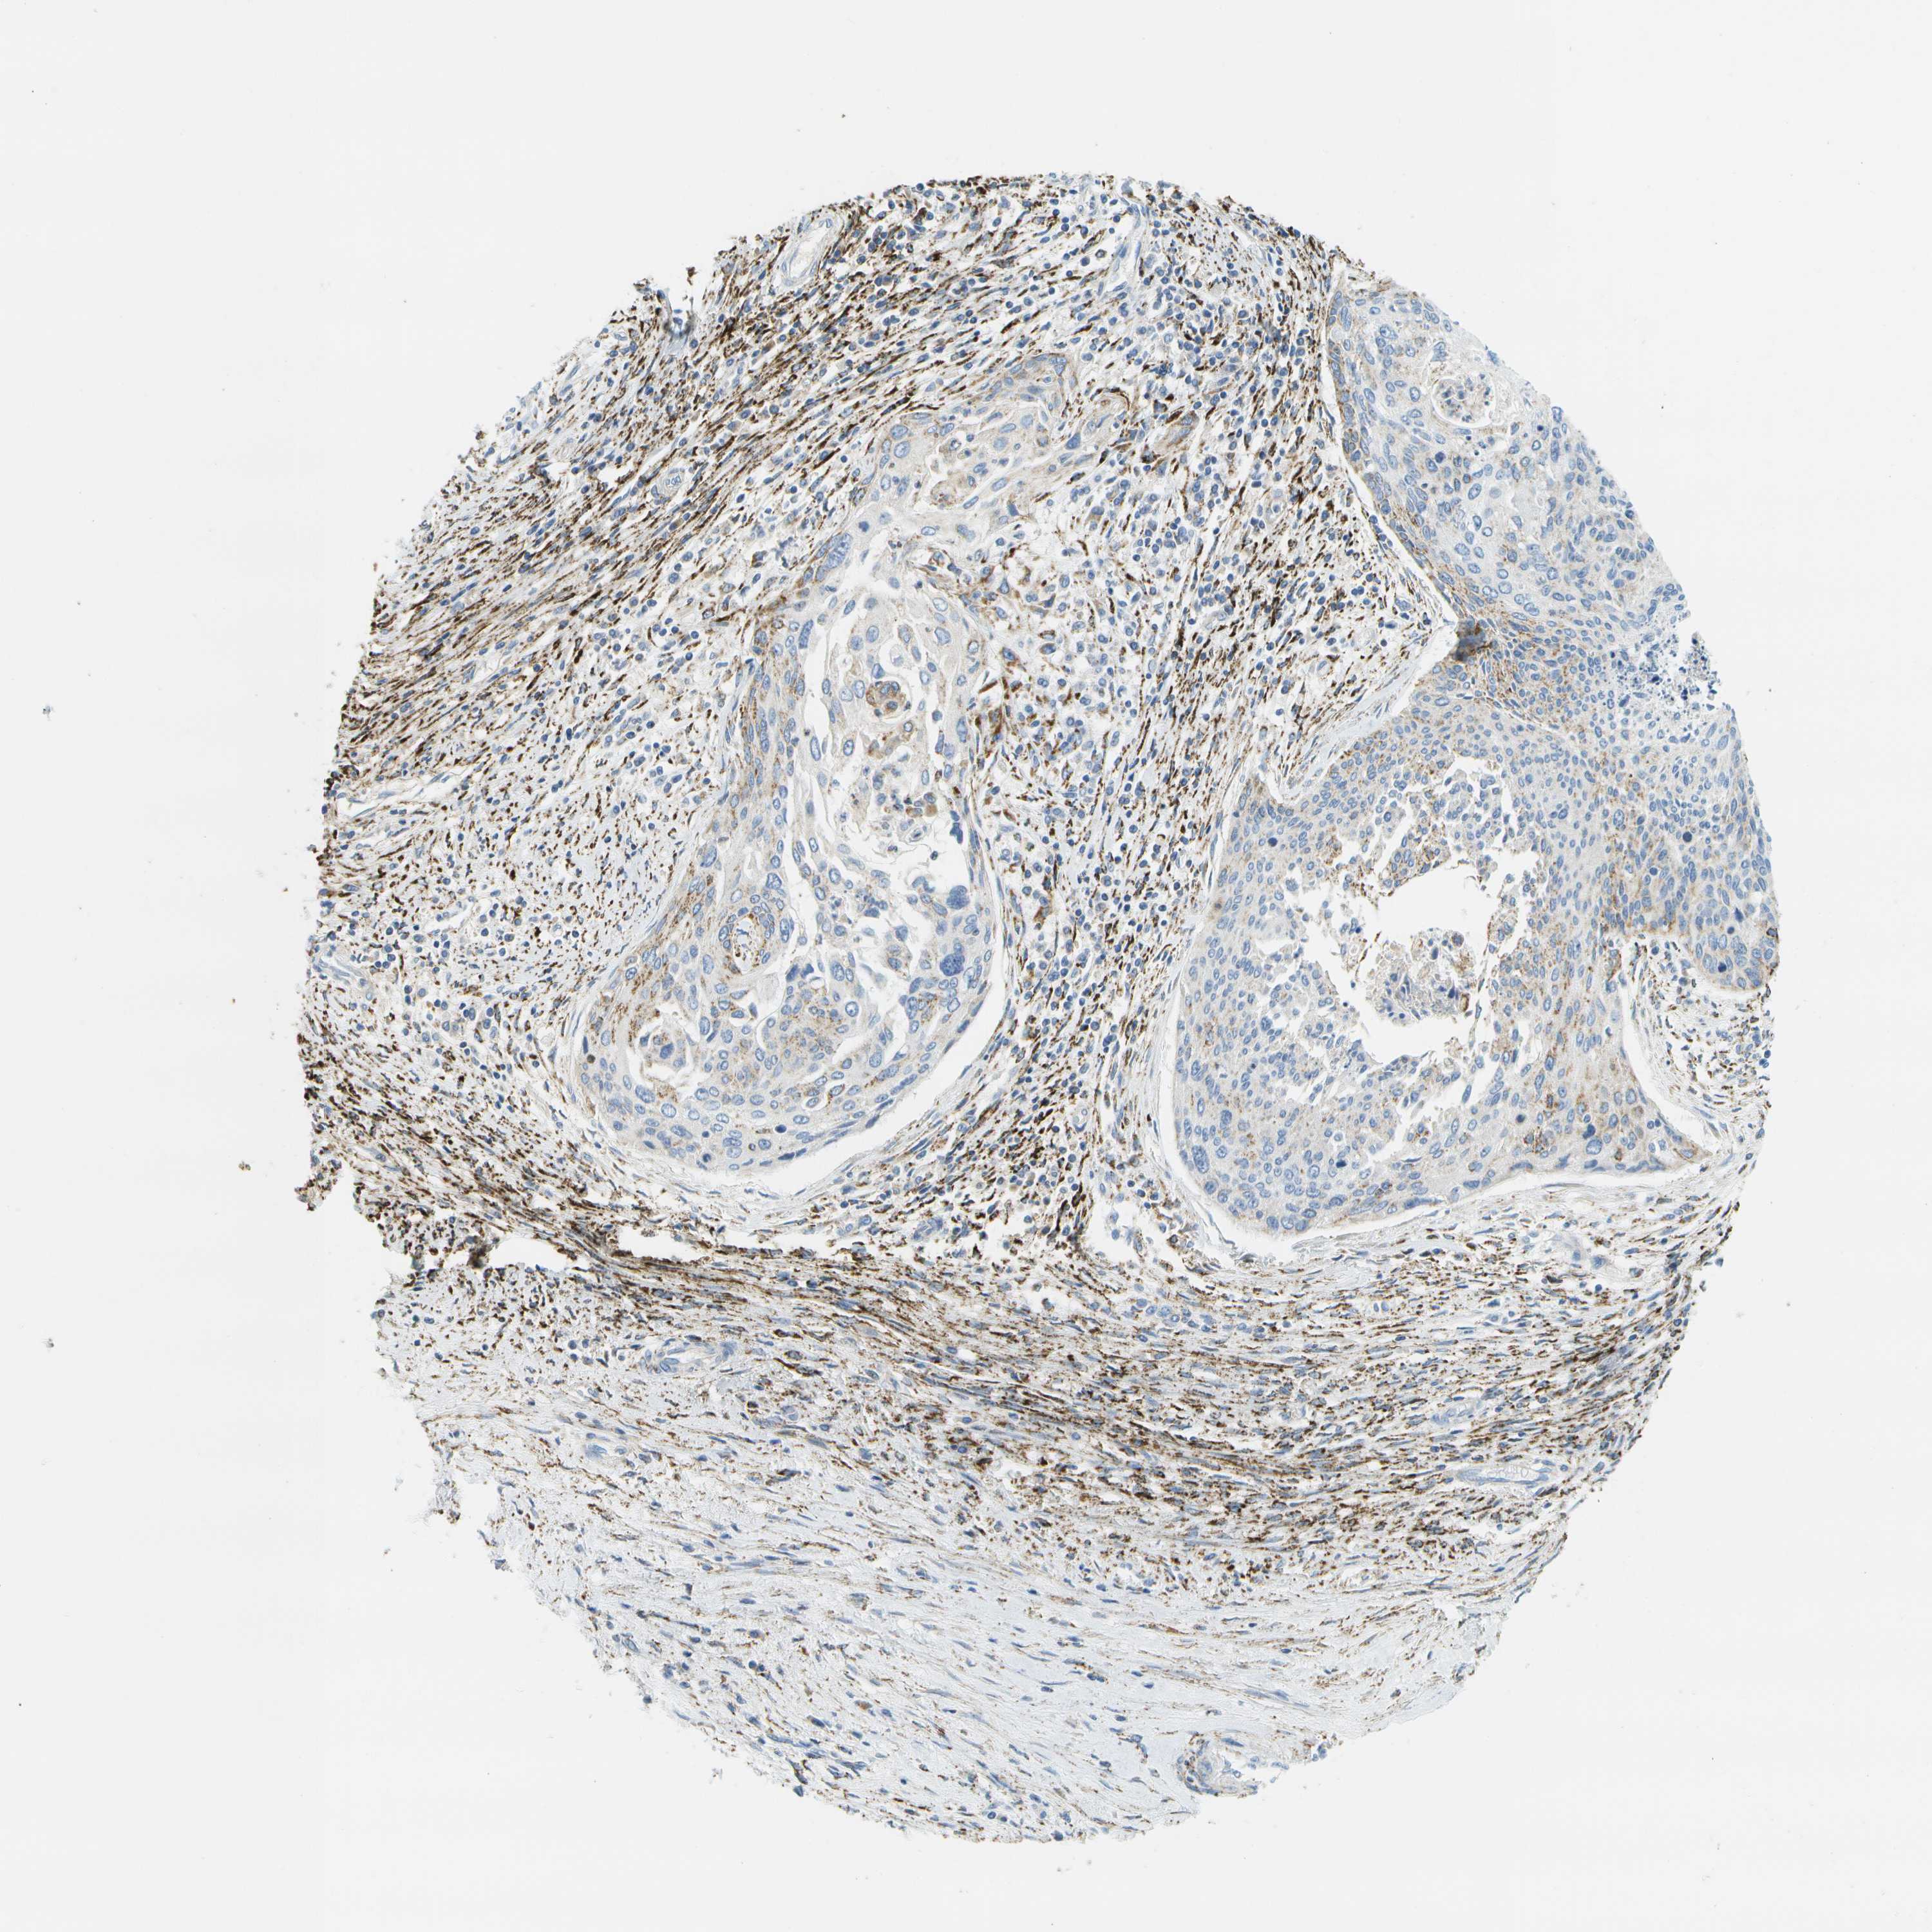

CERVICAL CANCER - Protein expressioni

A mouse-over function shows sample information and annotation data. Click on an image to view it in a full screen mode. Samples can be filtered based on level of antibody staining by selecting one or several of the following categories: high, medium, low and not detected. The assay and annotation is described here.

Note that samples used for immunohistochemistry by the Human Protein Atlas do not correspond to samples in the TCGA dataset.

Antibody stainingi

Antibody staining in the annotated cell types in the current human tissue is reported as not detected, low, medium, or high, based on conventional immunohistochemistry profiling in selected tissues. This score is based on the combination of the staining intensity and fraction of stained cells.

Each image is clickable and will lead to virtual microscopy that enables deeper exploration of all samples and also displays staining intensity scores, fraction scores and subcellular localization as well as patient and tissue information for each sample.

Antibody HPA017379

Staining

High

Medium

Low

Not detected

Intensity

Strong

Moderate

Weak

Negative

Quantity

>75%

75%-25%

<25%

None

Location

Nuclear

Cytoplasmic/membranous

Cytoplasmic/membranous,nuclear

Squamous cell carcinoma, NOS

Adenocarcinoma, NOS